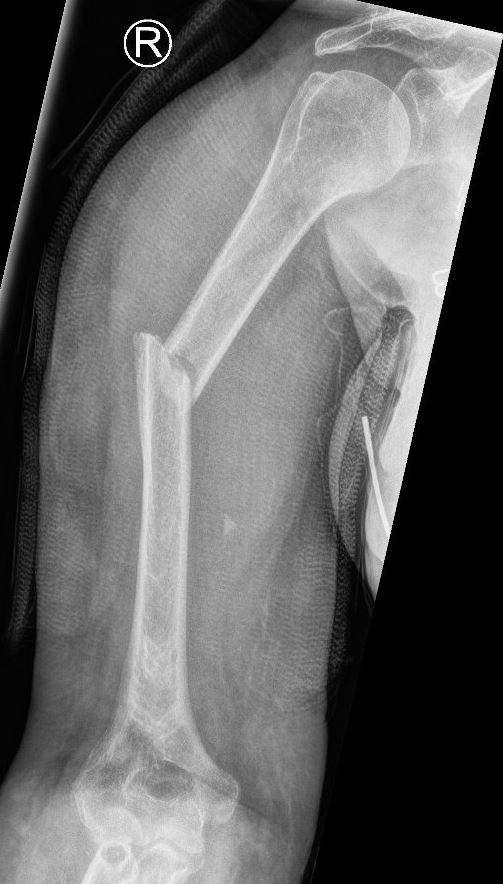

Wanneer de schacht van het bovenarmsbot breekt, dan komt dit meestal door een val op de schouder of op een (uitgestrekte) bovenarm, dan wel door een directe klap tegen de bovenarm. De klachten kenmerken zich door veel pijn in de bovenarm met een onmogelijkheid de bovenarm te bewegen. Een bloeduitstorting is vaak pas na enkele dagen zichtbaar. Een Röntgenfoto kan de aanwezigheid en het beloop van de breuk aantonen.

Indien u geopereerd wordt, zal de traumachirurg proberen de breukdelen van de schacht weer in de juiste vorm en richting aan elkaar te zetten. Hiervoor heeft uw traumachirurg verschillende opties, afhankelijk van het type breuk en de voorkeur van uw chirurg. Veel gebruikt is een pen in de mergholte van het bot, die via de schouder of via de elleboog kan worden ingebracht. De pen wordt vervolgens met dwarse schroefjes aan het begin en het einde van de pen vastgezet. Een andere optie is het gebruik van platen en schroeven om de verschillende breukdelen stevig aan elkaar vast te zetten. Voor het plaatsen van een plaat is wel een grotere snede nodig dan voor een pen. Welke operatie u uiteindelijk krijgt, is afhankelijk van de eigenschappen van de breuk, uw eigen toestand en de voorkeur van de chirurg.